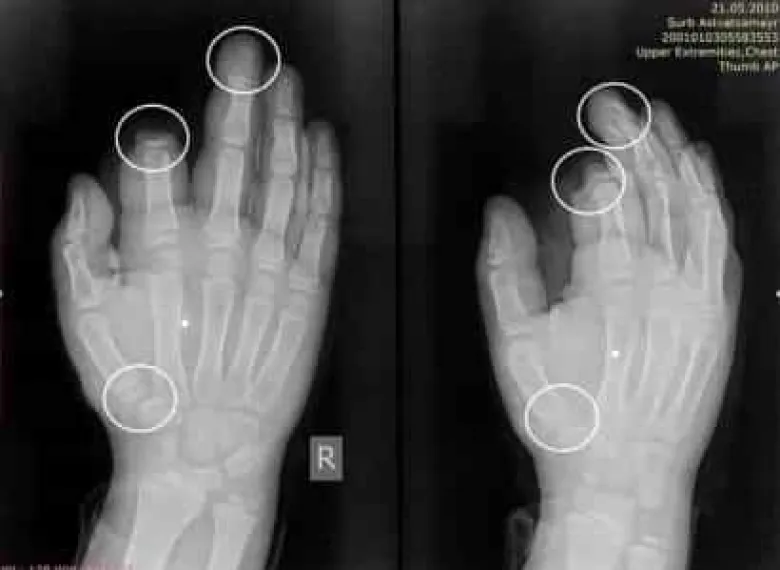

Ամանորի գիշերը պայթուցիկներից ստացած վնասվածքներից ամպուտացվել է 10-ամյա տղայի մատը: Այս մասին իր ֆեյսբուքյան էջում տեղեկացնում է «Սուրբ Աստվածամայր» ԲԿ մամուլի պատասխանատու Գևորգ Դերձյանը:

«Ամանորի գիշերը «Սուրբ Աստվածամայր» ԲԿ են դիմել պայթուցիկներից ու հրավառություններից տուժած 6 անձ։

Նրանցից 4-ը ստացել են ամբուլատոր բուժօգնություն, իսկ 2-ը շարունակում են մնալ բժիշկների հսկողության տակ։

10-ամյա տղայի մոտ ամպուտացված է եղել մեկ մատը (պոկված մատը վերականգնման ենթական չի եղել), իսկ մյուս մատները հաջողվել է փրկել։ Իսկ 16-ամյա տղան պայթուցիկի հետևանքով մատների կոտրվածքներ է ստացել, վնասվել են նաև ձեռքի մկանները»,- գրել է նա: